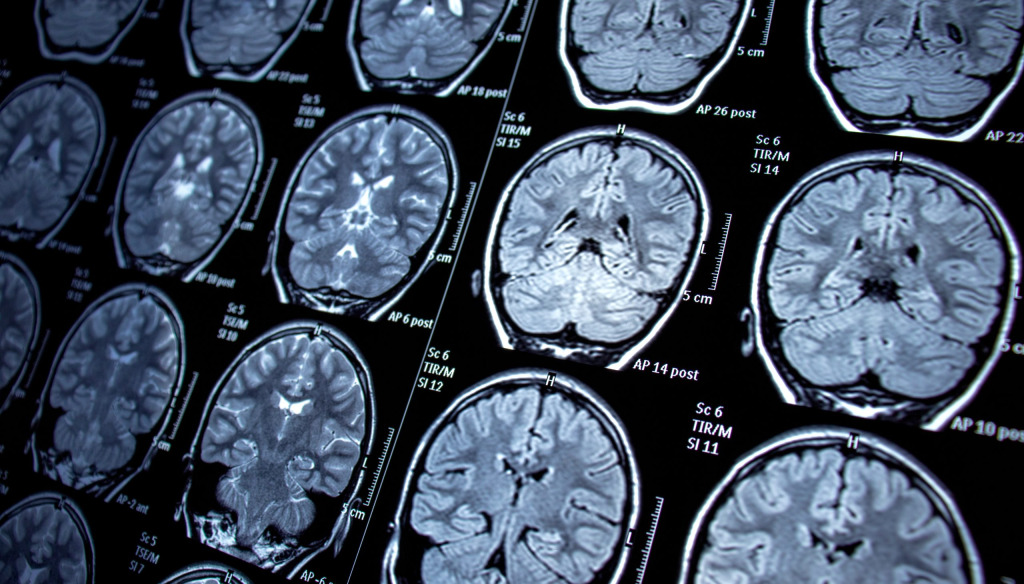

Fact: Tourette syndrome is a neurological condition

Yes. TS is a brain neurodevelopmental disorder that causes involuntary motor and vocal tics – movements or sounds a person can’t fully control. It’s thought to involve the interaction of multiple gene variations and environmental factors. Tourette Syndrome is not caused by bad behaviour, poor parenting, or emotional problems.